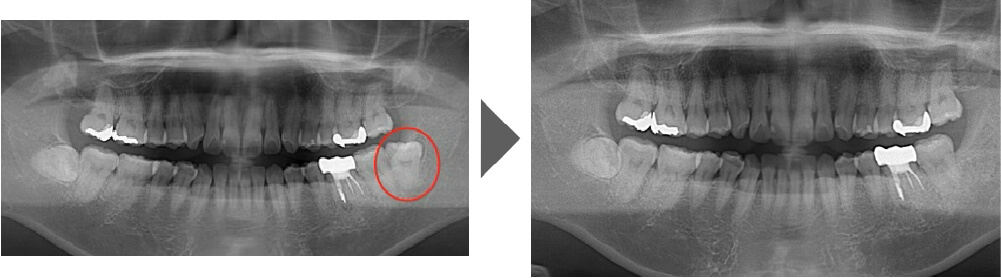

抜歯症例③

ご覧いただいた通り、生えている向きが真横に近い状態で、 通常は時間を要する抜歯です。

【抜歯所要予約時間】

15分

(麻酔の時間があるので処置自体はもっと短いです)